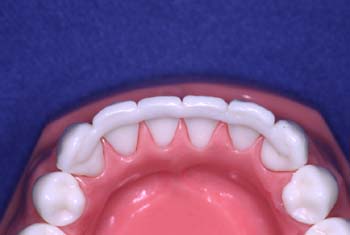

Estético y cómodo, el retenedor de Ribbond está finalizado.

A diferencia de un alambre de metal, Ribbond ofrece una estética superior y no es visible.